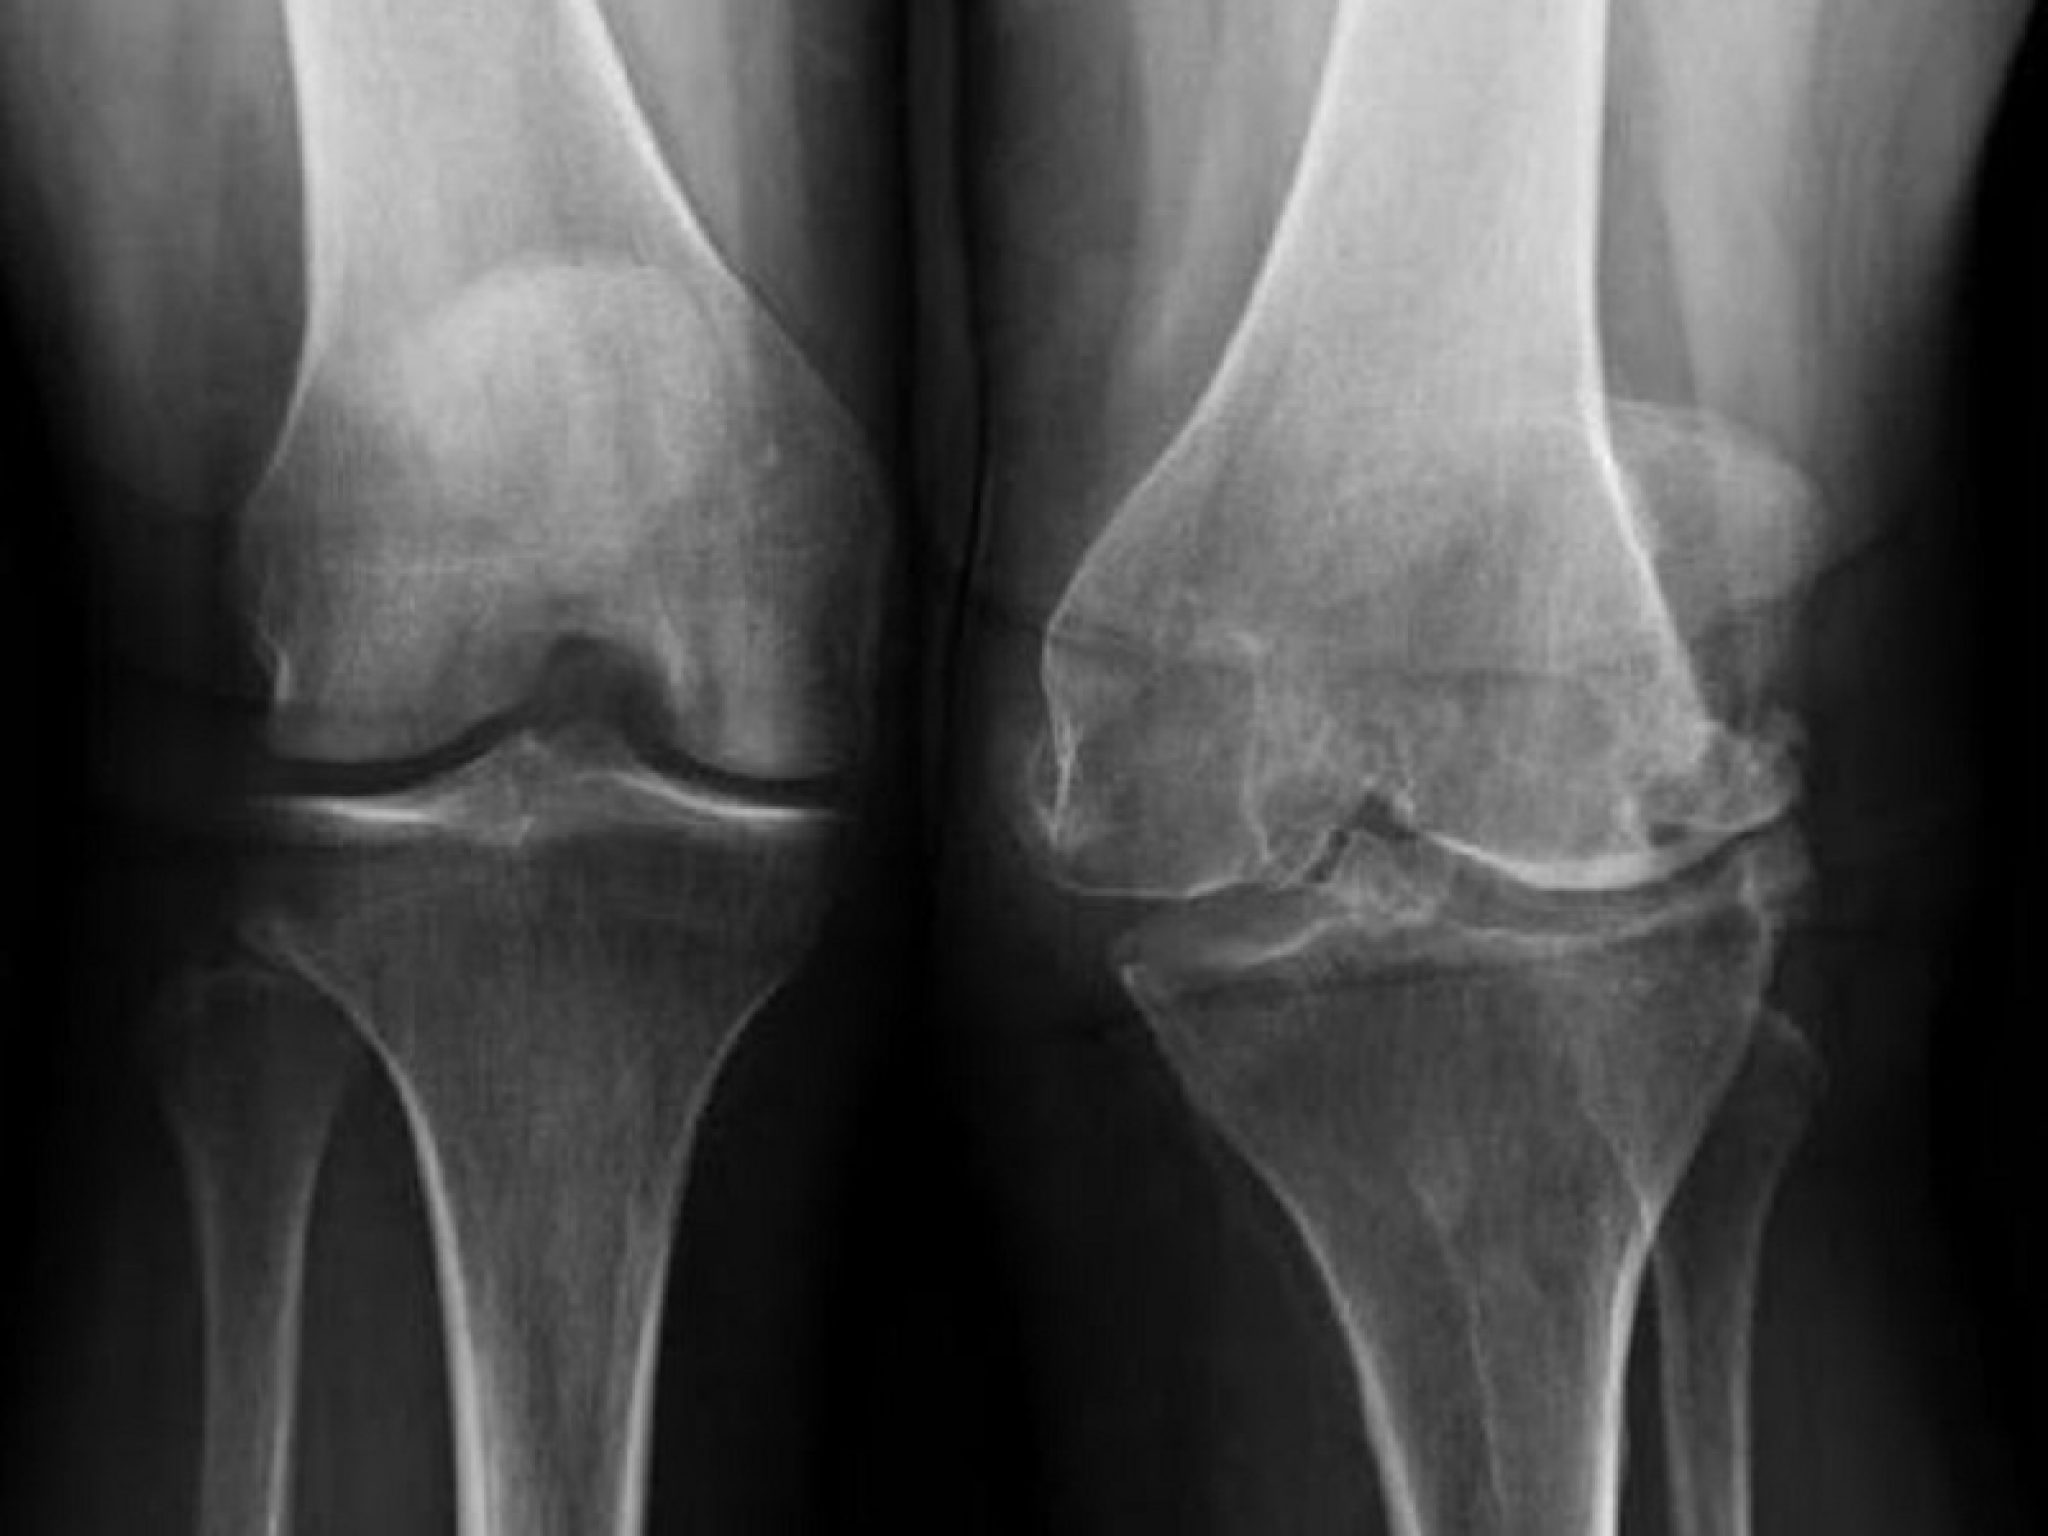

Медицинские состояния: Септический артрит коленного сустава